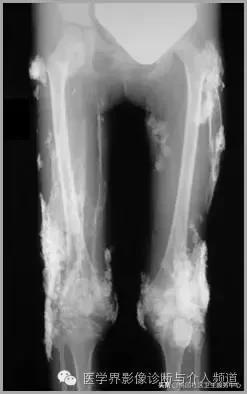

皮肌炎